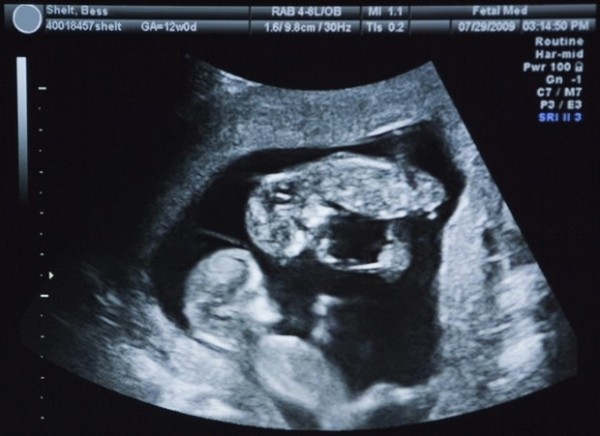

На одном из плановых УЗИ выяснилось, что у нас будет двойня. Мы обрадовались невероятно! Представлять, что ребенка будет два и разных, непохожих, было прекрасно и волшебно!.. Я сразу вспомнила о братьях-двойняшках моей мамы: блондин и брюнет, разного роста, с разными характерами. В голове возникали умилительные картинки моего будущего двойного счастья.

На 20-й неделе я узнала о том, что жду тройню! Причем искать третьего во время УЗИ стали целенаправленно: цифры на пренатальном скрининге были странными, вводившими врачей в недоумение. Лишь один из специалистов предположил, что детей не двое, а больше.

Так я узнала, что стану сразу многодетной мамой.